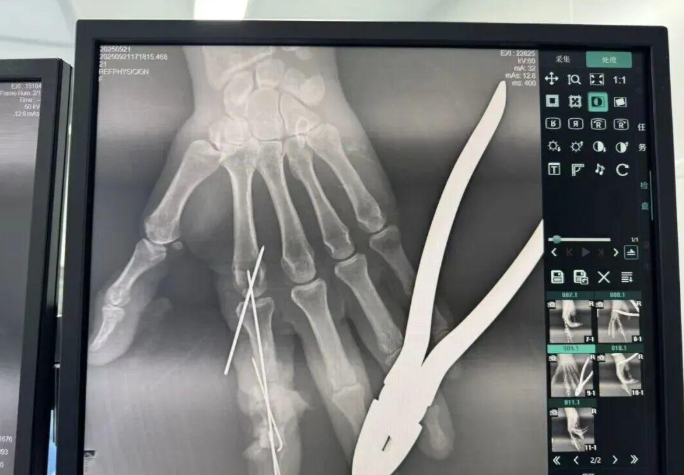

為確保手術(shù)成功,楊志主任特別聯(lián)合劉金海主任組成多手術(shù)組協(xié)作團(tuán)隊,充分發(fā)揮梯隊配合優(yōu)勢,反復(fù)研討后確定了“組合式”手指再造方案:利用右足踇趾的皮瓣、末節(jié)甲床及部分趾骨,聯(lián)合第二趾的趾間關(guān)節(jié),再取部分髂骨進(jìn)行精確植骨,將這些組織精密拼裝,重建一個兼具良好外形和功能的新示指。

手術(shù)當(dāng)天,多手術(shù)組梯隊配合的優(yōu)勢得到充分體現(xiàn)。無影燈下,楊志主任與團(tuán)隊各司其職、緊密配合,一場漫長的生命接力就此展開。在放大40倍的專業(yè)手術(shù)顯微鏡下,醫(yī)生們開始了精細(xì)操作。楊志主任在術(shù)后解釋道:“患者需要吻合的血管直徑僅0.5-1.0毫米左右,末節(jié)手指的毛細(xì)血管更是細(xì)如發(fā)絲。我們必須將移植組織與手部的血管、神經(jīng)、肌腱進(jìn)行精準(zhǔn)吻合,確保移植組織通血成活。這不僅要求醫(yī)生有扎實的顯微外科技術(shù),還要具備專業(yè)的整形外科審美能力,才能讓再造的指尖既好用又好看?!?/p>